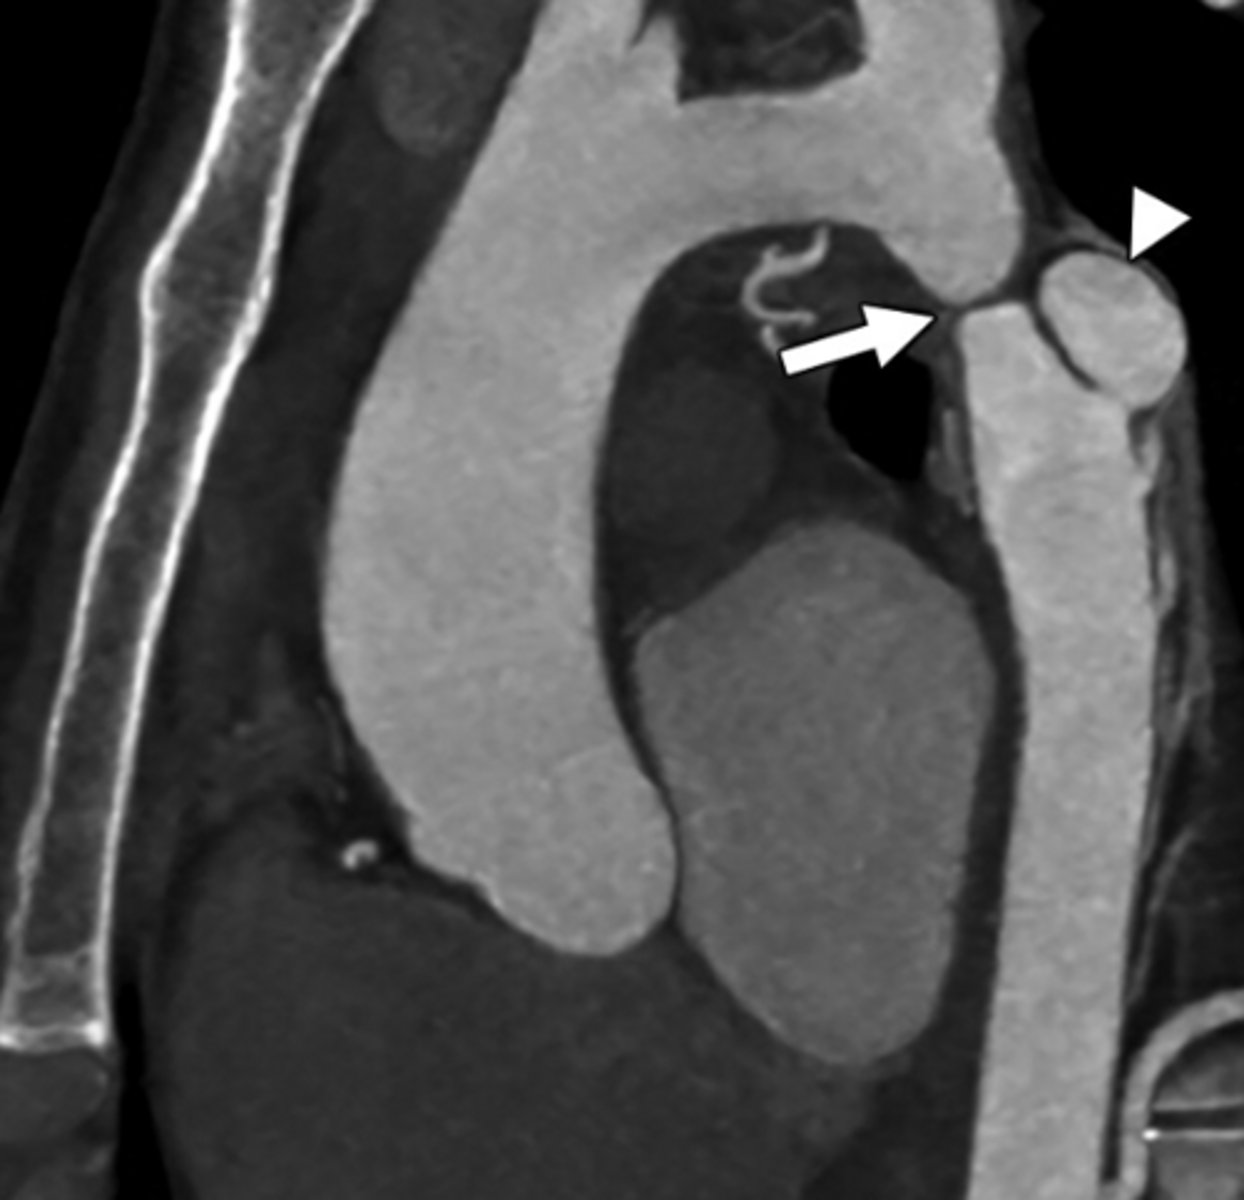

What is coarctation of the aorta?

Congenital narrowing of the aorta.

What are the key features of infantile coarctation of the aorta?

Symptomatic in early childhood, tubular hypoplasia of the aortic arch, occurs proximal to a PDA.

What are the key features of adult coarctation of the aorta?

Narrowing opposite a closed ductus arteriosus, distal to the great vessels from the aortic arch.

What is the chest radiograph finding in coarctation of the aorta?

Figure 3 sign.